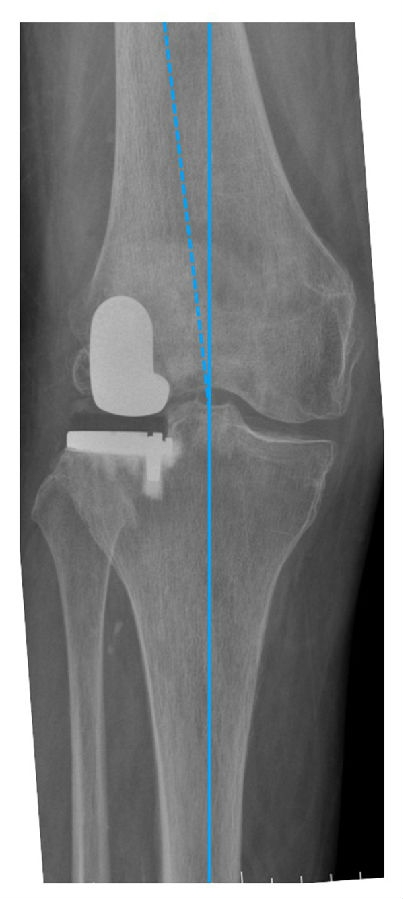

关键技术3:理想的下肢力线

HIP-Knee-Ankle line 外翻3-5°,胫骨角10-12°

LUKA 术后畸形矫正不足,保持轻微的外翻。建议LUKA术后保留3 ~ 5°外翻。